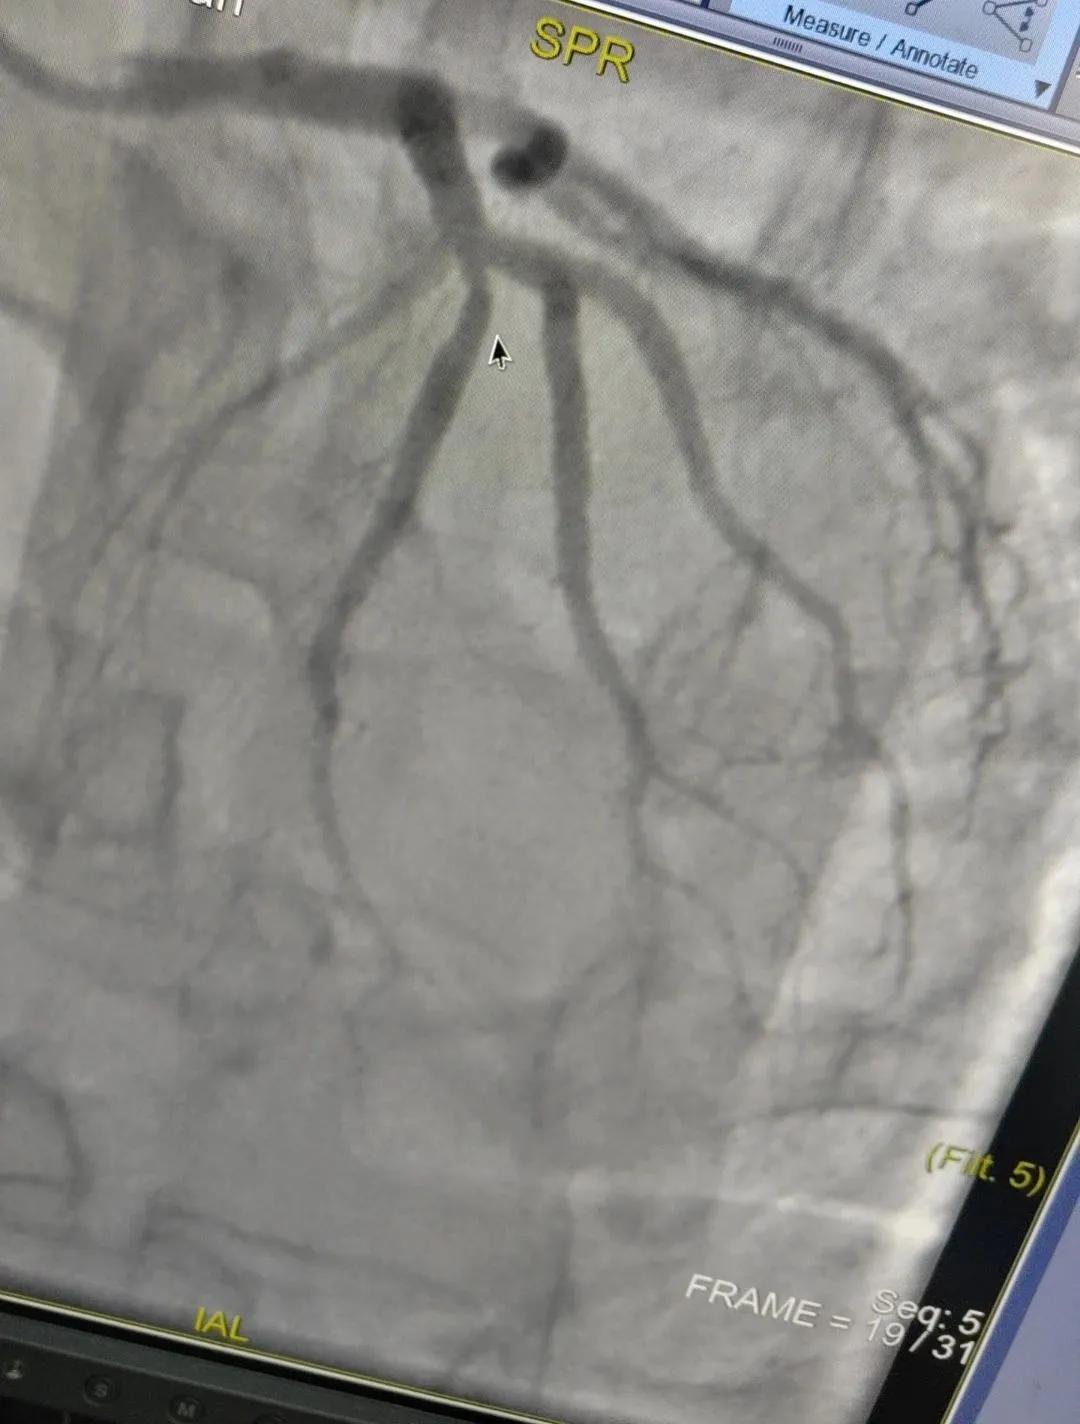

術(shù)中心血管造影顯示:LAD中段發(fā)出D1處可見約50%節(jié)段性狹窄,RCA中段狹窄約40%,PLA可見約70%狹窄病變。

腦血管造影顯示:左側(cè)頸內(nèi)動(dòng)脈嚴(yán)重遷曲,左側(cè)大腦前動(dòng)脈未顯影,左側(cè)大腦中動(dòng)脈M1中段以遠(yuǎn)未顯影,M1近段串珠樣嚴(yán)重狹窄,顱底可見少量煙霧血管,后交通動(dòng)脈未開放;右側(cè)頸內(nèi)動(dòng)脈嚴(yán)重遷曲。右側(cè)大腦前動(dòng)脈A1段嚴(yán)重遷曲。